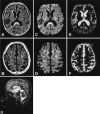

Marchiafava-Bignami disease (MBD), a rare complication of chronic alcoholism, is characterized by primary demyelination of the corpus callosum. We report two cases of MBD in which fluid-attenuated inversion recovery (FLAIR) and diffusion-weighted imaging studies revealed symmetrical hyperintense lesions in the cerebral cortex (particularly in the lateral-frontal regions) in addition to the callosal lesions, which suggests an association of diffuse cortical lesions such as Morel's laminar sclerosis with MBD.